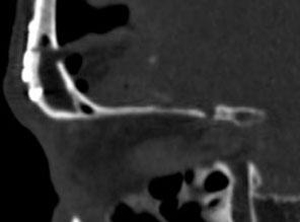

Ⅱ 60歳代男性

外眼筋四角錐内悪性リンパ腫

右視力・視野障害、眼球突出を主訴として来院した。摘出手術後視機能は改善し、眼球突出は消失した。骨条件術後CTでは、眼窩壁が整復され術前と同じ形状を維持していることがわかる。

術後 骨CT